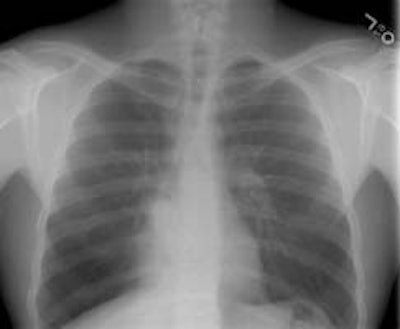

Alveolar Sarcoid:

The female patient shown in the images below presented with complaints of dyspnea on exertion. Although many disease processes were entertained in the differential for the findings on her exams, a transbronchial biopsy was performed and a diagnosis of sarcoid was made histologically.

The CXR revealed bilateral, large nodular opacities with poorly defined

margins: